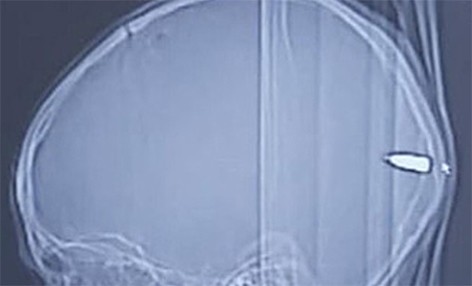

Ребенок из Восточного Иерусалима жаловался на сонливость. Медики обнаружили в его голове пулю. Об этом информирует Daily Mail.

31 июля родители мальчика заметили, что их ребенок ведет себя необыкновенно пассивно. Обеспокоенные этим фактом, они отвели малыша в больницу. Мальчик постоянно засыпал, и медики обнаружили на его голове ранку и застывшую кровь.

После томографии оказалось, что в затылке ребенка застряла пуля. Родители об этом не знали.

Через два часа после приезда в больницу малышу провели срочную операцию. Врач отметил, что ребенок не выжил бы, если бы пуля прошла немного под другим углом.

Мальчик восстанавливается после операции. Он может общаться и чувствует себя хорошо.